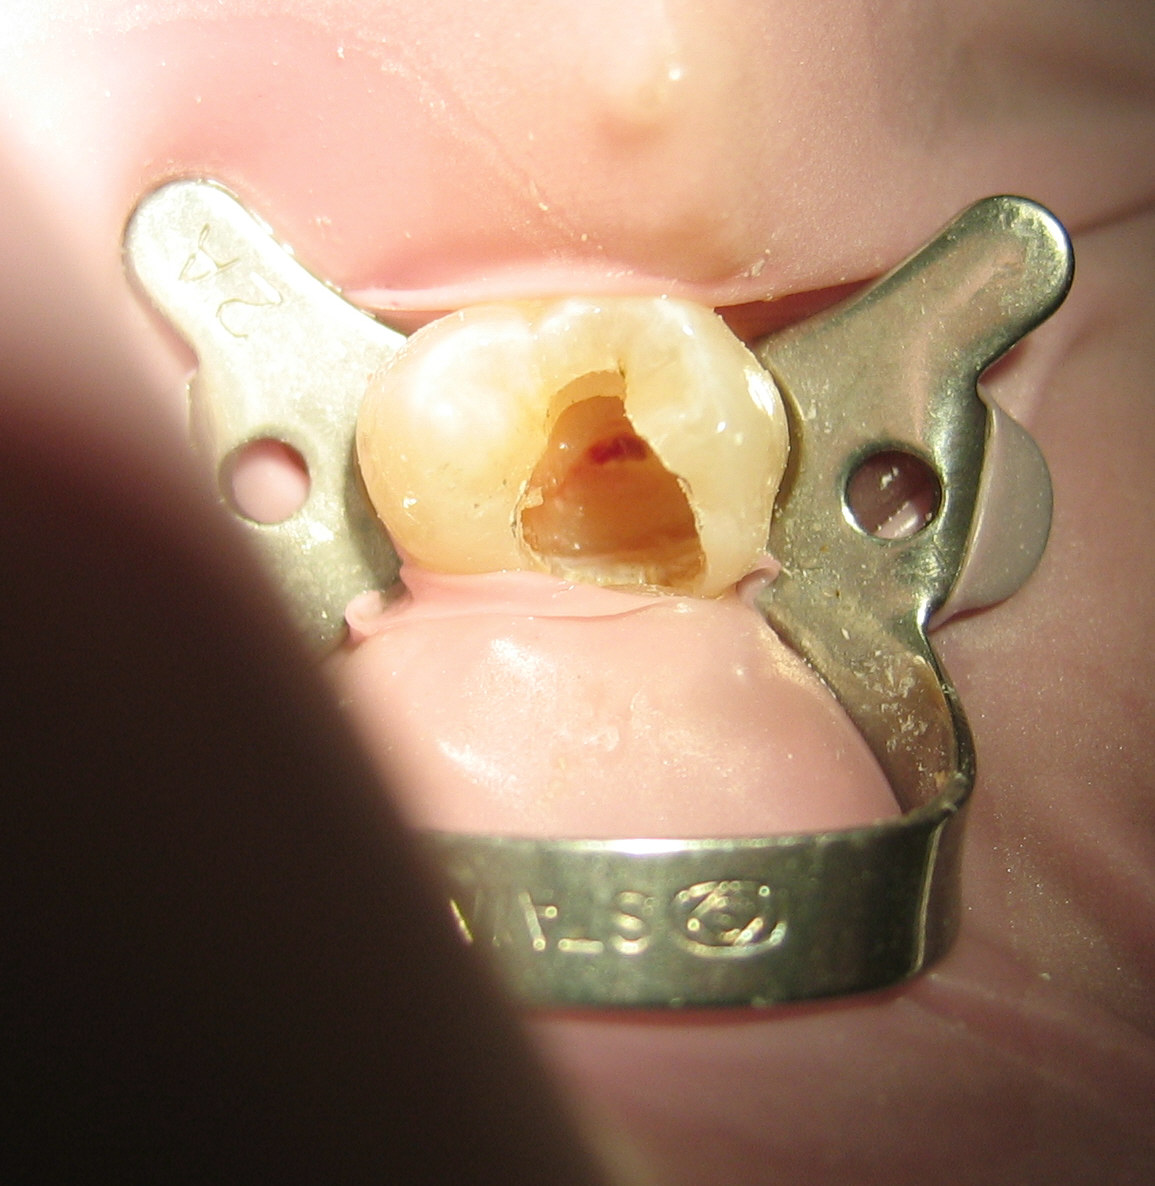

Pour comprendre un abces, il faut connaitre l'anatomie de la dent. Une dent est composee de trois couches : l'email (exterieur blanc, le materiau le plus dur du corps), la dentine (couche intermediaire jaunatre) et la pulpe (tissu mou central contenant les nerfs et les vaisseaux sanguins). Quand une carie depasse l'email et la dentine pour atteindre la pulpe, les bacteries entrent dans la chambre pulpaire, provoquent une necrose pulpaire, puis l'infection descend par les canaux radiculaires jusqu'a l'os de la machoire ou elle forme l'abces.

C'est le type le plus frequent (environ 70% des cas). L'infection part de l'interieur de la dent, plus precisement de la pulpe, et se propage par le canal radiculaire jusqu'a l'extremite (apex) de la racine. Le pus s'accumule dans l'os alveolaire autour de l'apex et forme l'abces. La cause principale est une carie profonde non traitee, une fracture dentaire exposant la pulpe, ou l'echec d'un ancien traitement de canal.

Sur une radiographie retro-alveolaire, un abces peri-apical apparait comme une zone sombre arrondie (radioclaire) au bout de la racine, signe de la destruction osseuse locale. Le traitement necessite de nettoyer le canal infecte (devitalisation ou traitement de canal endodontique) ou d'extraire la dent si elle n'est plus recuperable.

C'est la cause de 60 a 70% des abces dentaires. Une carie est une destruction progressive de la dent par les acides produits par les bacteries (principalement Streptococcus mutans). Au debut, la carie est limitee a l'email (indolore, reversible par fluoration). Elle traverse ensuite la dentine (sensibilite au froid, au sucre). Si elle n'est pas soignee, elle atteint la pulpe : les bacteries penetrent dans la chambre pulpaire, provoquent une pulpite aigue (douleur violente) puis une necrose pulpaire, et enfin un abces peri-apical.